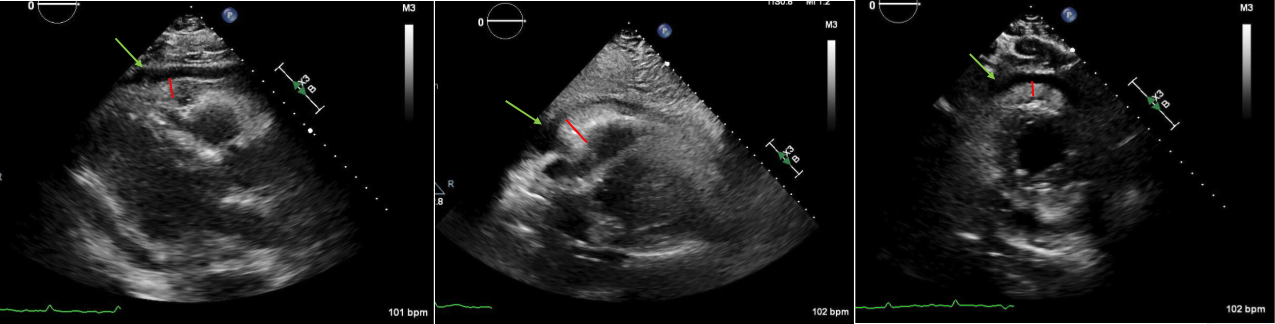

Abstract Body (Do not enter title and authors here): Case Description: A 71-year-old male presented to the hospital for dyspnea and chest discomfort for the past 2 weeks. He has a history of AAA status post stent and current tobacco use with emphysema. On admission, he was found to be tachycardic with rates reaching as high as 180 with systolic blood pressure of 89/61 and hypoxic with SpO2 of 80%. EKG revealed AFib with RVR with no acute ischemic changes. Troponins were negative and proBNP was 307. Infectious workup was negative. CTA chest showed no evidence of PE or dissection, however, moderate pericardial and bilateral pleural effusion was shown with mediastinal lymphadenopathy. After starting an esmolol and amiodarone drip, he converted to sinus tachycardia. TTE showed an EF 55%, echo dense debris measuring 2 cm with 1 cm effusion within the pericardial space resulting in significant compression of RA and RV. Findings were concerning for tamponade evidenced by invagination of RA and RV during systole and diastole respectively and greater than 50% variation and tricuspid inflow velocities with respiration. He was taken emergently to the OR for a pericardial window, thoracentesis, and chest tube. 300 mL and 400 mL of cloudy straw-colored fluid were removed from the pericardial and pleural space respectively. Fluid studies were negative for malignant cells and cultures remained negative. Repeat TTE showed an EF 55%, with epicardial fat pad and small posterior pericardial effusion. ANA testing was positive; however, other autoimmune studies are negative. His symptoms improved and he was discharged home.

Discussion: Cardiac tamponade is commonly caused by large pericardial effusions. Mild pericardial effusion less than 1 cm on TTE does not typically cause symptoms. However, the presence of significant pericardial debris can be problematic with minimal pericardial effusion. In this case, the patient developed cardiac tamponade complicated by AFib with RVR. Fortunately, hemodynamics and symptoms improved post pericardial window draining 300 mL of bloody fluid, but the diagnosis remains unknown given negative fluid studies. It's postulated that the debris is inflammatory in nature, but the absence of a diagnosis puts the patient at high risk for shock if the pericardial window fails. Patients with pericardial debris up to 2 cm on TTE with risk of developing pericardial effusion should be monitored with follow up TTE. Further studies are necessary to unveil the underlying etiology of large pericardial debris.